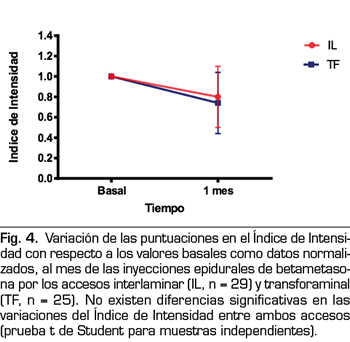

Los Índices de Intensidad e Interferencia también fueron reducidos por la inyección epidural de esteroides (Figuras 4 y 5). La betametasona administrada por la vía interlaminar parasagital redujo el Índice de Intensidad de 7,2 ± 1,2 a 5,8 ± 2,1 y el Índice de Interferencia de 7,0 ± 1,8 a 5,8 ± 2,5, en ambos casos una disminución estadísticamente significativa (p = 0,002 y p = 0,01, respectivamente; prueba t de Student para muestras pareadas). La betametasona administrada por la vía transforaminal redujo el Índice de Intensidad de 7,7 ± 1,6 a 5,7 ± 2,4 y el Índice de Interferencia de 7,7 ± 1,7 a 6,3 ± 3, reducción estadísticamente significativa (p = 0,0002 y p = 0,008, respectivamente). No hubo diferencias estadísticamente significativas entre ambos accesos al comparar la reducción de ambos índices.